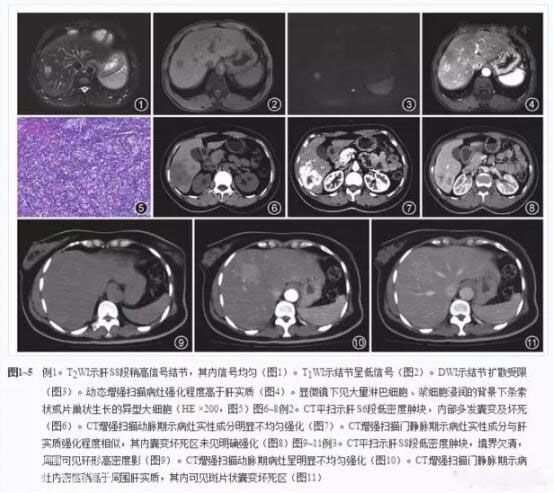

非霍奇金淋巴瘤影像-医学影像图,_医学图库

腹腔及腹膜后多发肿大淋巴结,会是什么呢

腹腔及腹膜后多发肿大淋巴结,会是什么呢